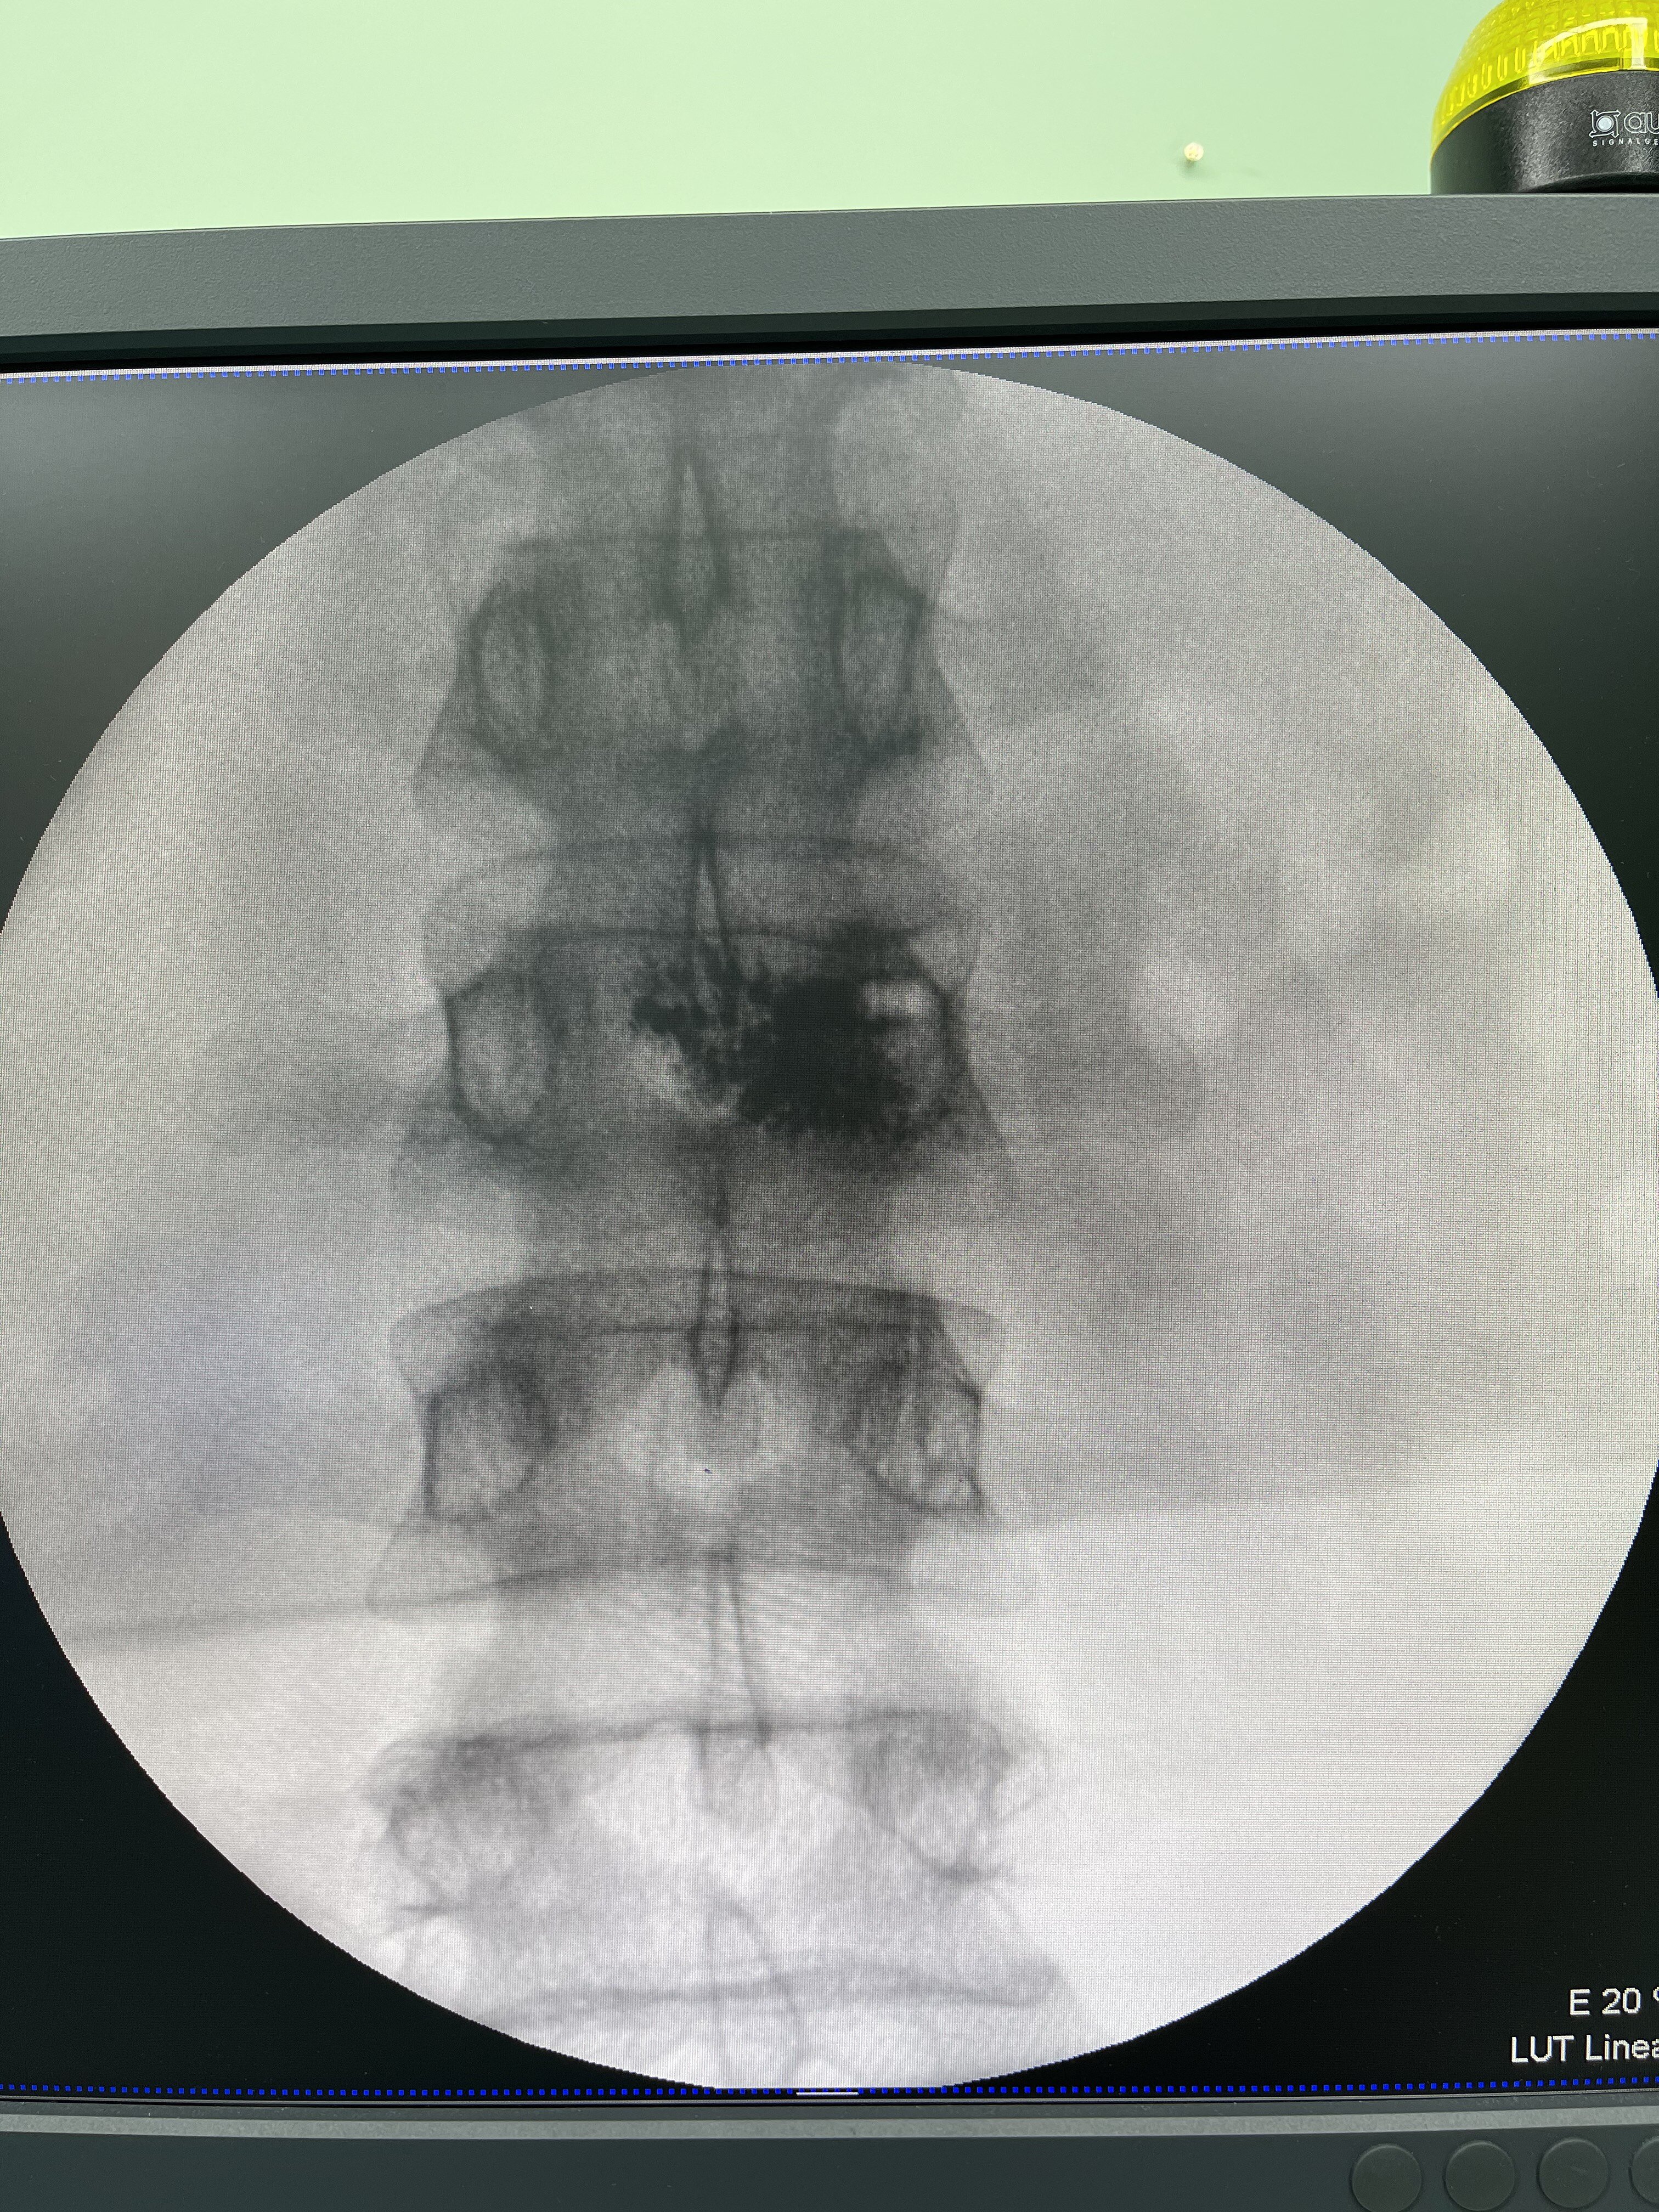

2.病理性骨折 所谓病理性骨折就是指在没有收到暴力打击,仅在轻微外力、甚至是“打喷嚏”、弯腰动作出现的中轴骨(脊柱、肋骨、骨盆)和四肢骨折。其原因就是肿瘤细胞侵蚀、破坏了骨的正常结构、硬度和强度下降,导致轻微的外力作用下就出现骨折。

出现这几种常见的情形后,一、做好及时就医,前往专科就诊。二、相信骨转移仍然可治(a.药物治疗:骨保护药物;b.放射治疗:止痛、抗肿瘤;c手术干预:经皮穿刺椎体球囊扩张成形术、骨成形术等微创手术,病理性骨折开放手术,脊柱转移瘤的分离手术?立体定向放疗技术结合等)。三、相信合理的规范治疗,骨转移瘤仍然可以达到带瘤生存,部分单发转移积极治疗后,甚至可达到无瘤生存。四、由此,保持良好的心态,积极阳光的接受治疗同样对康复很关键。